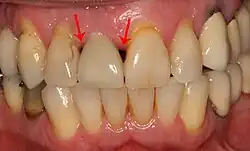

Показанием к имплантации является отсутствие зуба (адентия) по любой причине. [3] [4]

При утрате одного или нескольких зубов костная ткань в этом месте со временем истончается из-за отсутствия жевательной нагрузки, что ведёт к деформации челюстно-лицевой системы. Наличие имплантата обеспечивает адекватную нагрузку на кость челюсти подобно естественному корню зуба, поэтому истончения костной ткани не происходит. Каждый человек, который потерял один или несколько зубов в результате различных травм, болезней или разрушения зубов, имеют показания для имплантации зубов. Люди преклонного возраста также могут пройти процедуру имплантации, поскольку определяющим фактором её осуществления является скорее состояние здоровья, нежели возраст. Вопрос о том, возможно ли проведение дентальной имплантации, решается специалистом — стоматологом после тщательного медицинского обследования конкретного пациента и детального осмотра состояния его зубов.